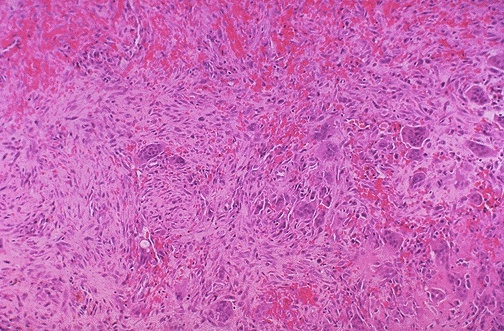

Image 6.4

The blood interdigitates with numerous multinucleated giant cells in a fibroblastic stroma.